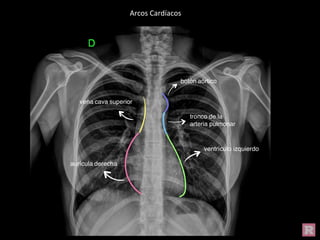

Arcos Cardíacos

Estructuras vasculares y cardíacas en Radiografía de Tórax Normal